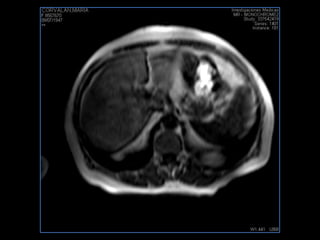

PROTOCOLO abdomen COR T2, AXIAL supresion grasa AX T1 +SAG T2  CON   GADOLINIO :  COR T1+AX T1(DIN) SAT: NO  FASE: RL THK: 6MM  COIL:  GAP: (FACTOR 1.4) 2MM FOV: 40 CM NEX:2 SINCRONIZACION RESPIRATORIA EN 3 O 4 CICLOS ALE

resonancia de abdomen